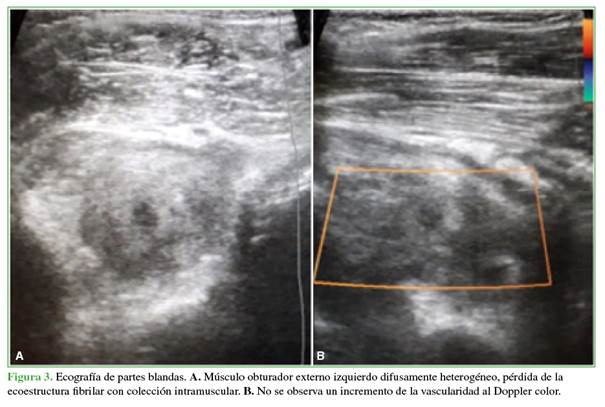

Tras caracterizar la lesión, se efectuó un procedimiento quirúrgico de emergencia junto con el servicio de estudios por imágenes. Se procedió inicialmente a la artrocentesis de cadera guiada por ecografía, en la cual no se obtuvo un líquido purulento y luego a una punción percutánea guiada por ecografía del absceso localizado en el área inguinal profunda. Se obtuvo una secreción francamente purulenta espesa del obturador (5 cc) con localización muscular intrasustancial, que fue enviada para cultivo. El procedimiento resultó de gran ayuda, porque nos permitió asegurarnos de que el cuadro infeccioso era extrarticular (Figuras 3 y 4). Se continuó con una punción articular debido a los síntomas de presentación del paciente, la primera posibilidad fue el compromiso de la cadera y el procedimiento de elección es la artrocentesis con la cual se descartó el compromiso articular. Con la tomografía computarizada, se logró identificar una colección intramuscular; sin embargo, consideramos importante por epidemiología descartar que esta provenga de la cadera; por este motivo, las intervenciones se realizaron en este orden.